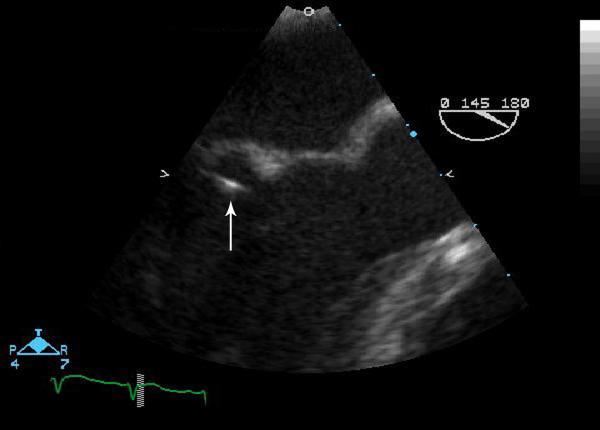

Over a period of 6 months we encountered three cases of invasive Streptococcus intermedius infection presenting as hepatic abscesses, brain abscess, and endocarditis. We confirmed our microbiologic diagnosis through 16S sequencing and found a common virulence gene in each case.

在6个月的时间里,我们遇到了3例侵袭性中间型链球菌感染病例,分别表现为肝脓肿、脑脓肿和心内膜炎。我们通过16S测序证实了微生物学诊断,并在每个病例中发现了一个共同的毒力基因。